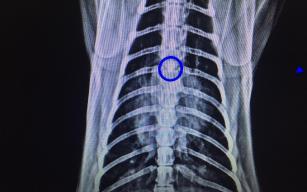

Kedinin soluk borusundan çıkan cisim şoke etti